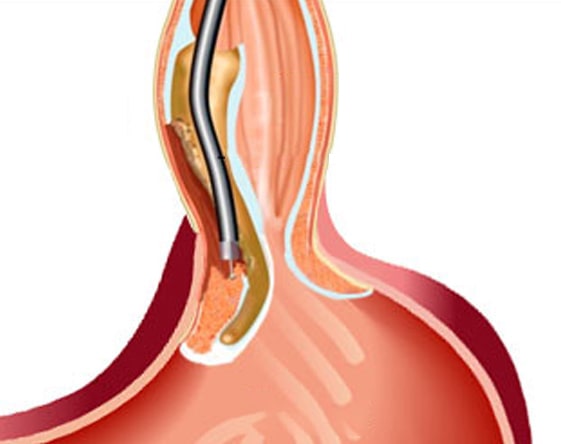

I had difficulty swallowing for 5 years. I was diagnosed with achalasia last year. I had taken treatment for a long time but there was no relief. I was also losing weight. I was also advised to undergo surgery. I came to know about the POEM procedure at SR Kalla Hospital. It was painless and I was discharged after 2 days. It has been 1 year and I have significant relief in swallowing. My weight has also increased. Thanks for the care

Painless endoscopy is one of the advanced procedures adopted for diagnosing the abnormalities in the stomach, particularly the small intestine. SR Kalla Hospital has a team of trained doctors, anesthetists, and the latest equipment to perform this endoscopic procedure. The major benefit of this procedure is that the patient does not experience any major discomfort.